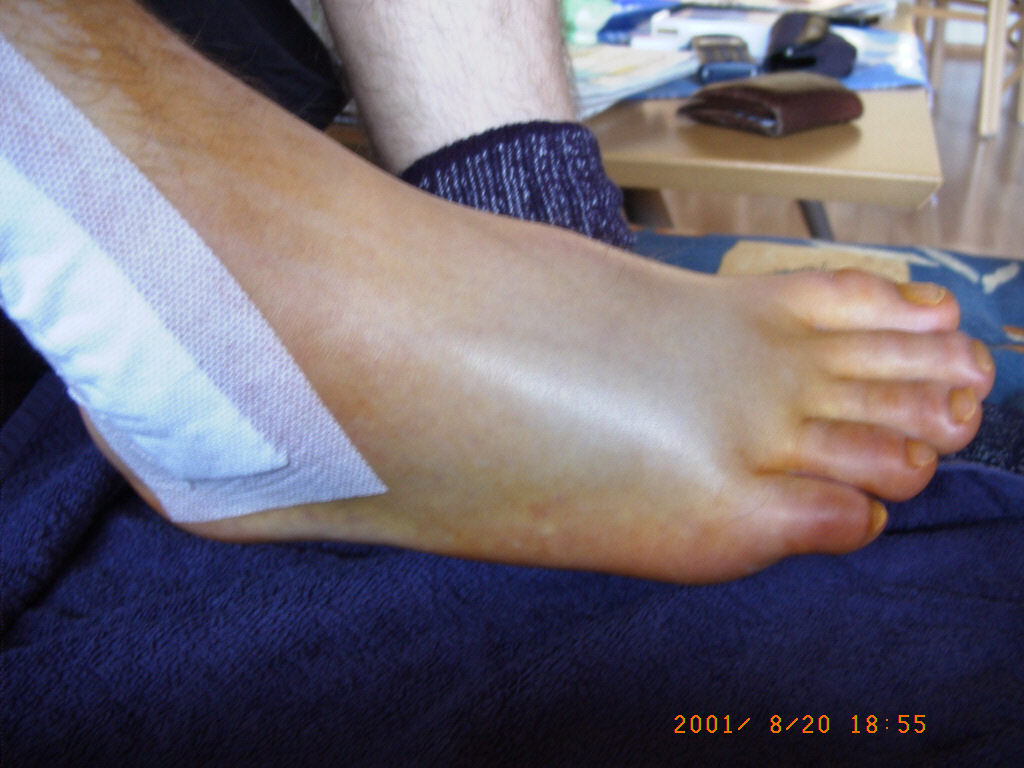

Die Fäden wurden am 28.08.2001 gezogen.

Sechs Wochen durfte ich nicht auftreten (keine Belastung). Ab der siebten Woche (26.09.2001) durfte mit 20kg und ab der achten Woche (03.10.2001) mit 40kg belastet werden.